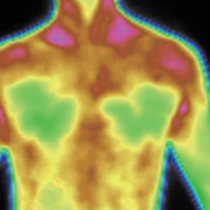

Assistance in syndrome differentiation in TCM

It can form the temperature distribution image of the human body by obtaining the infrared radiation signals of different strengths of body parts. It can assist in syndrome differentiation in TCM, physical assessment in TCM, meridian point exploration and treatment effect evaluation. In terms of treatment effect evaluation, it is possible to specify the location, onset time, duration and effect degree of drugs, acupuncture or other treatment methods, objectively and accurately evaluating treatment methods.